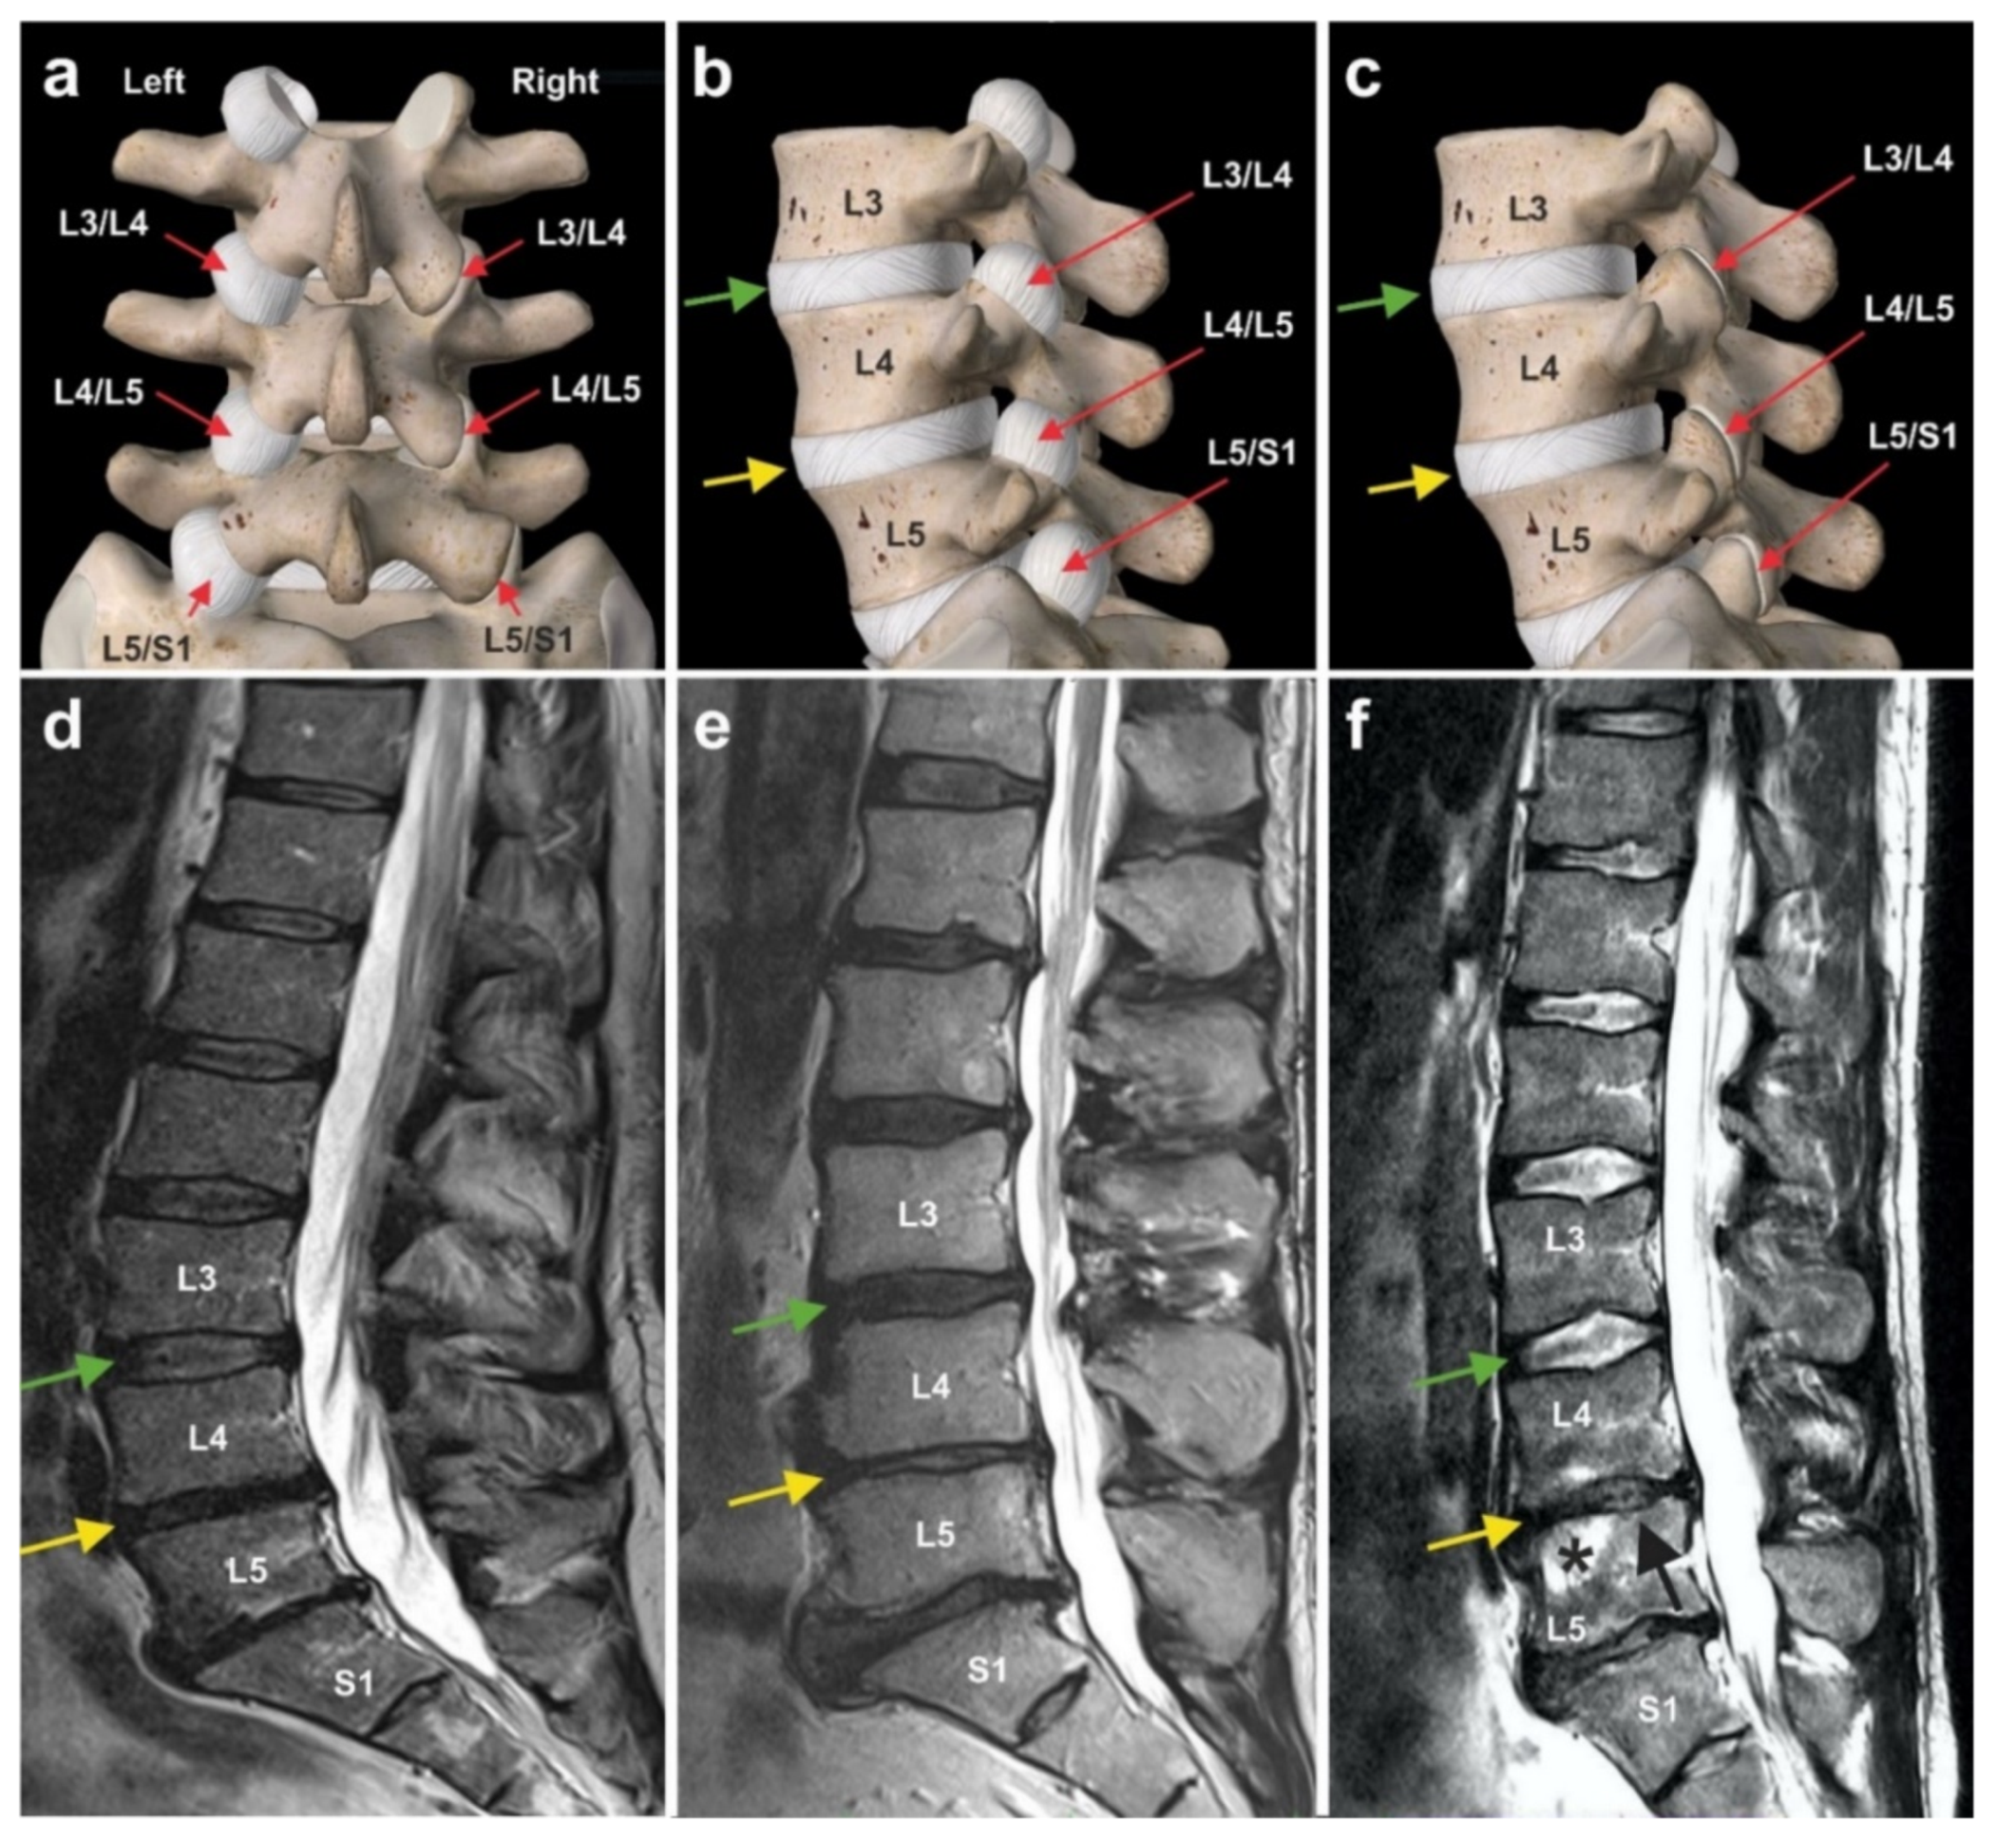

6.3. Chronic, Recalcitrant Low Back Pain Caused by Lumbosacral Facet Syndrome